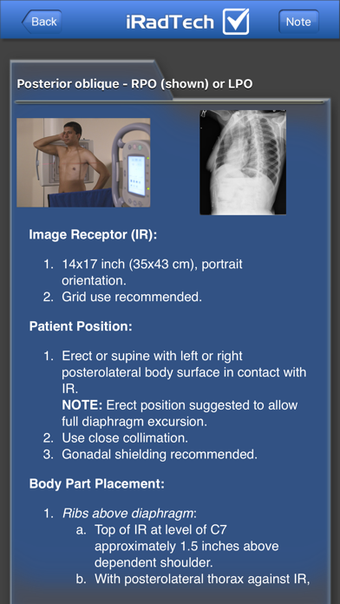

IRadTechè un programma completo per iPhone, che fa parte della categoria 'Medicina'.

Informazioni su IRadTech per iPhone